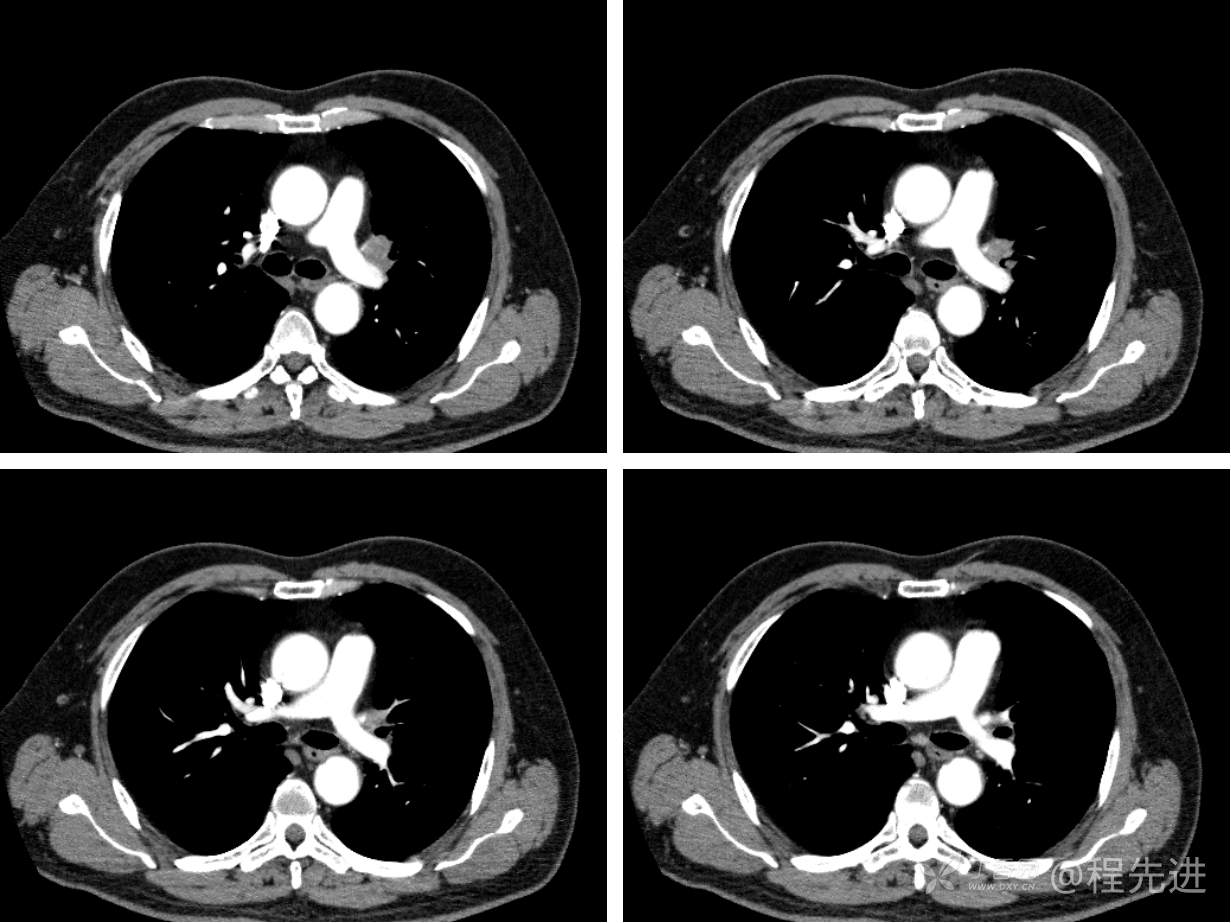

现病史概要:患者入院前约半月无明显诱因下出现咳嗽、胸闷症状,无明显发热症状,咳少量白痰,无明显咯血、喘息、头晕等不适,就诊我院查胸部CT示上纵膈肿物,左肺上叶支气管内肿物,现为行进一步治疗收入胸外科,患者近来饮食睡眠尚可,二便如常。